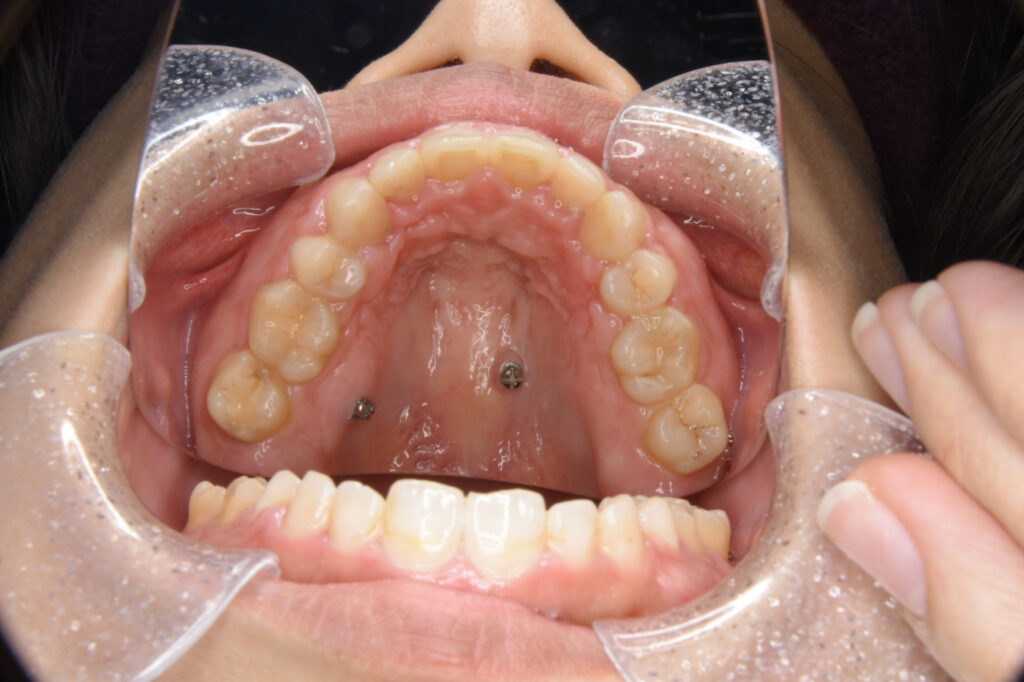

前歯が出ているために口が閉じにくく、口元が目立つことに悩まれていた方です。早期の改善を望まれていたため、抜歯とワイヤー矯正、歯科矯正用アンカースクリューによる治療を実施しました。

治療の内容上顎左右側第一小臼歯を抜歯。上顎舌側下顎唇側ワイヤー矯正装置、口蓋に歯科矯正用アンカースクリュー2本を用いた矯正治療。

期間・回数1年8ヶ月・20回

費用約115万円+消費税(矯正歯科治療は公的健康保険の対象外の自由(自費)診療となります。)